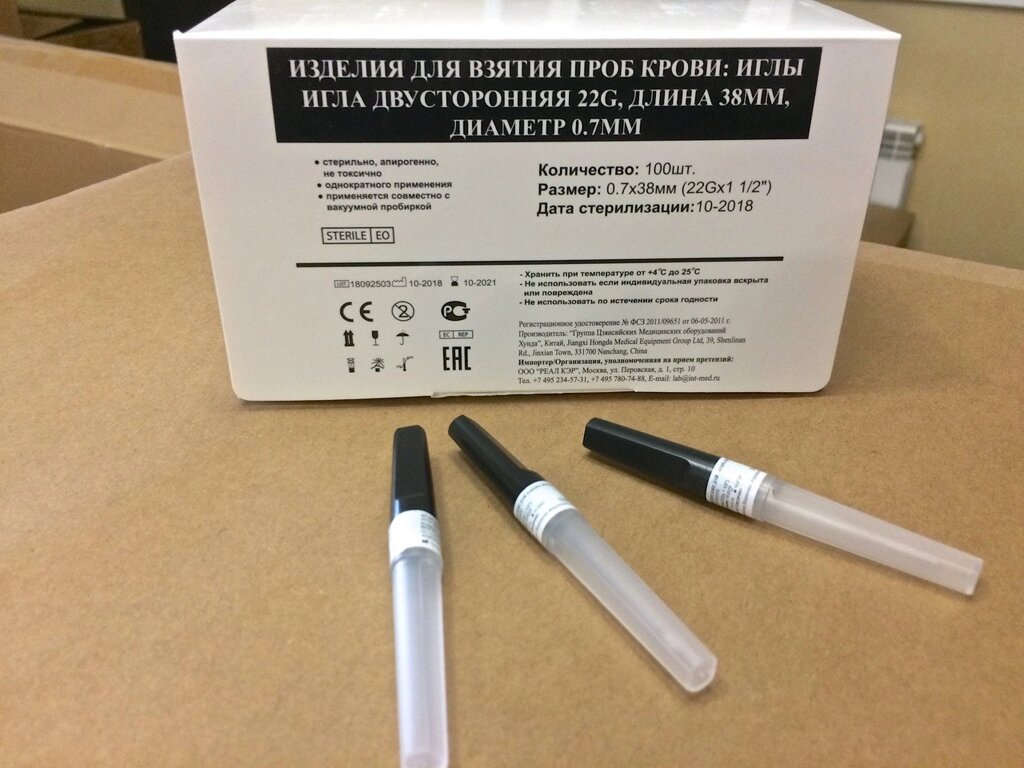

Фотографии игл с диаметром 18g